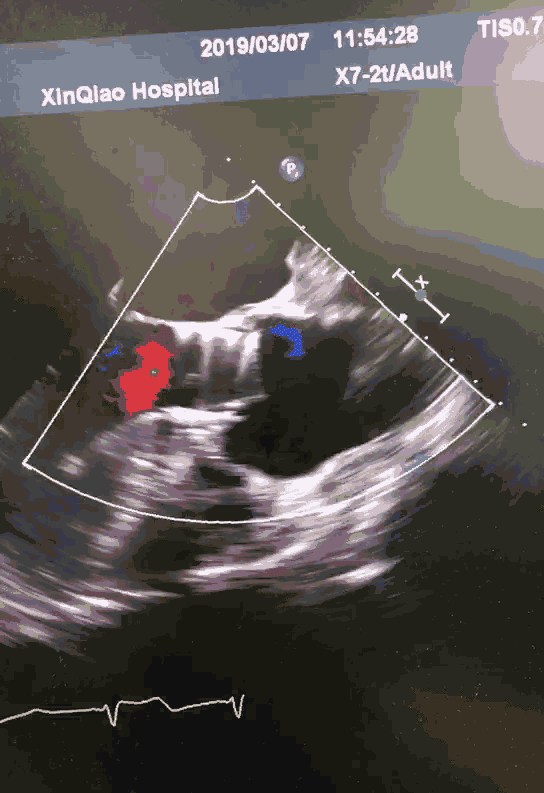

彩色多普勒心尖四腔心切面示人工二尖瓣前向血流速度增快,呈五彩镶嵌

二尖瓣关闭不全超声